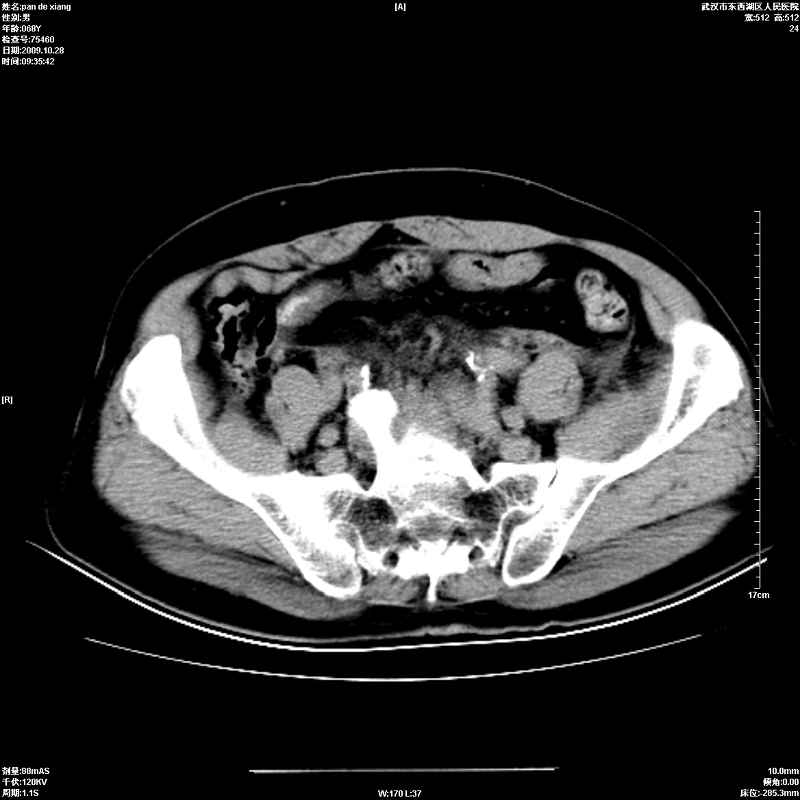

以下是引用杀毒软件在2009-10-28 20:41:00的发言:[br]结合临床考虑---白血病双肾改变或淋巴瘤。

以下是引用zxl51642在2009-10-29 9:59:00的发言:[br]结合临床“单克隆免疫球蛋白血症”,考虑双肾为继发损害并肾功能不全(尿中大量igg及少量iga、igm等大分子免疫球蛋白滤出所致继发损害),椎前软组织肿块为髓外造血。与浆细胞瘤有区别,平扫时有战友说的很清楚。